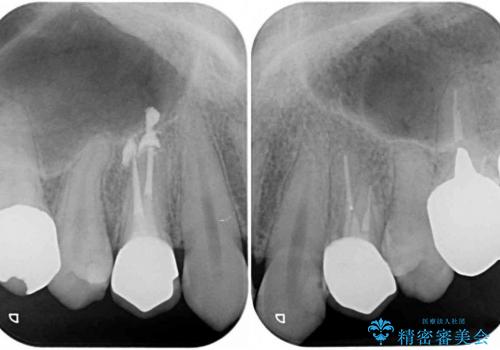

- 口を開けたときに目立つ銀歯を気にして来院された患者様です。

保険診療では銀歯となってしまうため、審美面の改善を目的として、オールセラミッククラウンにて補綴することとしました。

今回治療を行った小臼歯と呼ばれる歯は、保険診療ですと銀歯、またはプラスチックのクラウンとなってしまいます。プラスチックは装着したばかりは白いのですが、その後著しく変色をし、また強度も低いため、銀歯同様長期的に装着することはお勧めできません。

オールセラミッククラウンを装着したことで、審美性が改善されたことはもちろん、不適合な銀歯とは異なり、歯肉の腫れもきれいに引き、患者様には大変満足していただきました。